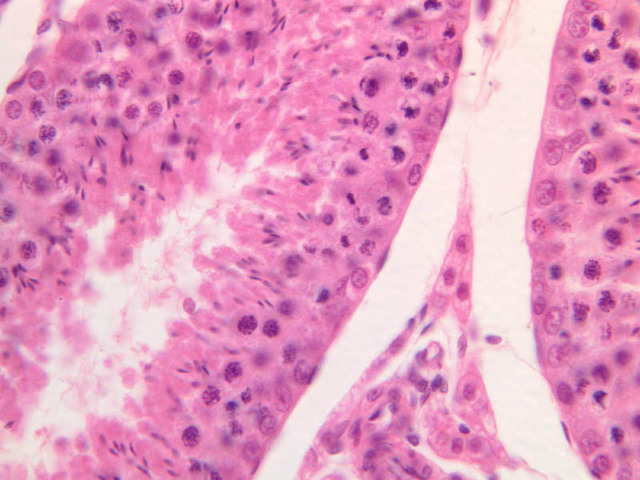

Both androgens and spermatozoa are produced by the testis. Androgen synthesis is accomplished by Leydig cells. Leydig cells are often arranged in clusters with their distinct nuclei displaying a prominent nucleolus (B-82 [2.5x, 10x, 20x-labeled, 40x-labeled]). These clusters are located in close proximity to small blood vessels or elements of the extensively developed testicular lymphatic system. What might this relationship facilitate? The abundant eosinophilic cytoplasm usually has vacuolated appearance. Observe the interstices at high magnification in slide B-80 (H&E [2.5x, 10x, 20x, 40x-labeled] [10x, 20x, 40x]). Be aware, however, that most of the empty-appearing interstitial spaces in these slides are artifacts of specimen preparation.

Sperm production, or spermatogenesis, encompasses two distinct series of events: one affecting mostly the nucleus, the other affecting mostly the cytoplasm. First, there is a series of events, known collectively as spermatocytogenesis, in which rounded diploid stem cells (spermatagonia) give rise to clusters of rounded haploid cells (spermatids). Then there is a series of events, known collectively as spermiogenesis, in which the round spermatid spins a long flagellum, undergoes compaction of its nucleus, transforms its Golgi complex into an acrosomal cap, and sheds nearly all of its cytoplasm to yield a spermatazoa. Bear in mind that if you are to develop a good sense of the dynamics of sperm production, you will have to examine a number of seminiferous tubules. This is because spermatogenesis is typified by complex waves of proliferation and differentiation that sweep both around the circumference and along the length of the seminiferous tubule. Using the high dry objective, search slide B-81 for a transversely sectioned seminiferous tubule (i.e. one that presents a round profile in which a large lumen is surrounded by an epithelial wall of uniform thickness). Observe that the peripheral surface is demarcated by a continuous layer of small flattened cells containing elongated basophilic nuclei. These are contractile myoid cells (similar to the myoepithelial cells of other glands), which aid in propulsion of the luminal contents towards the excurrent duct system (B-81, testis, PAS [2.5x-labeled, 10x, 20x. 40x-labeled]; [10x, 20x, 40x]). The clearly stratified seminiferous epithelium differs in appearance from one tubular profile to another and even from one part of a single tubule to another. The seminiferous epithelium is composed of two populations of cells: proliferating cells of the germinal spermatogenic series and nonproliferating Sertoli cells. Sperm production begins with mitotic division of cells located at the tubule periphery; later events occur progressively closer to the lumen. In typical H&E preparations of seminiferous epithelium it is the distinctive qualities of nuclei that stand out against poorly defined cytoplasm (B-80, testis, H&E [20x, 40x-labeled] [10x, 20x, 40x-labeled] [10x, 20x, 40x] [2.5x, 10x, 20x, 40x]; B-82, testis, H&E [2.5x, 10x, 20x, 40x] [2.5x, 10x, 20x, 40x] [10x, 20x, 40x] [10x, 20x, 40x]). Thus, in your study of seminiferous epithelium, it is nuclear appearance that will enable you to distinguish the following cell types:

Spermatids

Spermatids are located next to lumen of the seminiferous tubule, where they undergo an elaborate differentiation process (spermiogenesis) that requires about 7 weeks and involves condensation of nuclear chromatin, compaction and elongation of the nucleus, shedding of nearly all cytoplasm and formation of a motile flagellum (tail). Spermatid nuclei vary in size, condensation of chromatin and shape according to the stage of spermiogenesis that they represent; however, all of them are smaller than the nuclei of any of the antecedent cell types. Spermatids at different stages of spermiogenesis may be present in a single tubule.